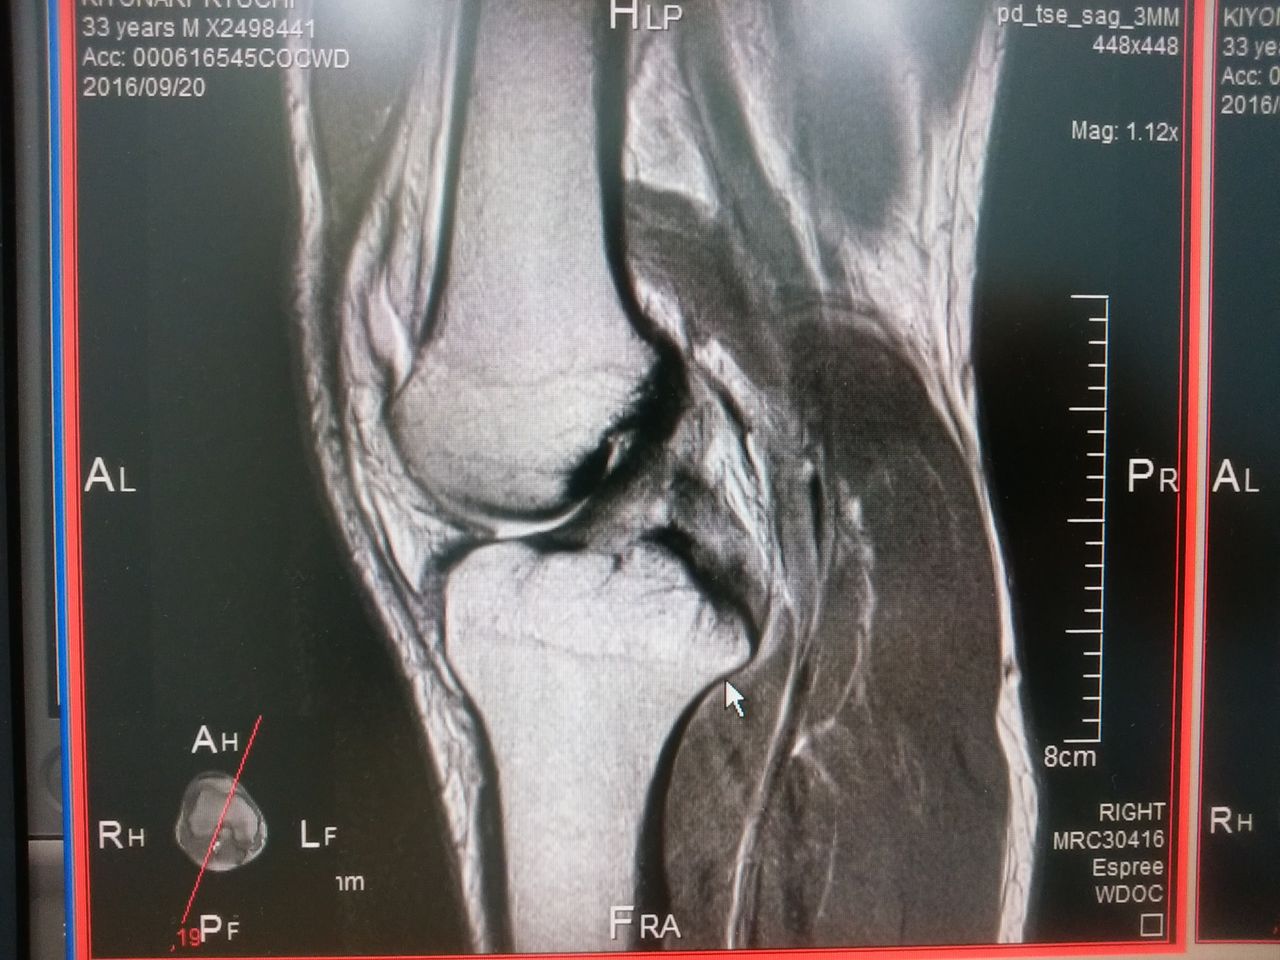

2016年11月08日 プロライダー イギリスのMRI イギリススーパーバイク選手権で 戦っているプロライダークラッシュに より帰国 イギリス現地のMRIもって帰って きました、 膝の前十字靭帯は かようじて 大丈夫のようです! 保存で直します タグ :#練習用